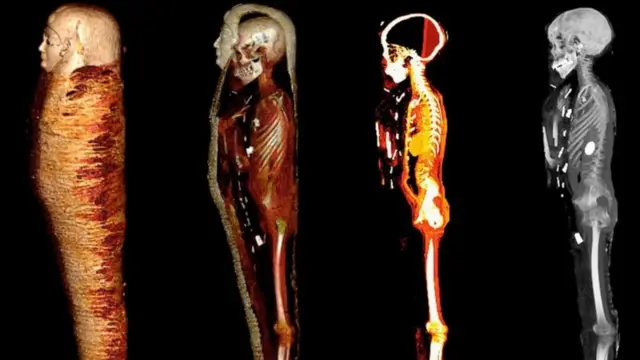

ਤਸਵੀਰ ਸਰੋਤ, .N. SALEEM, S.A. SEDDIK, M. EL-HALWAGY

ਕਾਹਿਰਾ ਯੂਨੀਵਰਸਿਟੀ ਦੇ ਡਾ. ਸਹਿਰ ਸਲੀਮ ਦੀ ਅਗਵਾਈ ਵਿੱਚ ਇੱਕ ਟੀਮ ਨੇ ਸੀਟੀ ਸਕੈਨਰ ਰਾਹੀਂ ਇਸ ਮਮੀ ਦਾ ਅਧਿਐਨ ਕਰਨ ਦਾ ਫ਼ੈਸਲਾ ਕੀਤਾ ਅਤੇ ਉਨ੍ਹਾਂ ਦੇ ਫ਼ੈਸਲੇ ਨੇ ਬਹੁਤ ਕੁਝ ਬਦਲ ਦਿੱਤਾ।

ਮਮੀ ਦੀਆਂ ਤਸਵੀਰਾਂ ਤੋਂ ਪਤਾ ਲੱਗਿਆ ਕਿ ਮ੍ਰਿਤਕ ਦੀ ਲਾਸ਼ ਅੰਦਰ 21 ਤਰ੍ਹਾਂ ਦੇ ਵੱਖ-ਵੱਖ 49 ਤਾਵੀਜ਼ ਸਨ ਜਿਨ੍ਹਾਂ ਵਿੱਚ ਕਈ ਸੋਨੇ ਦੇ ਬਣੇ ਸਨ। ਇਸੇ ਕਰਕੇ ਇਸ ਮਮੀ ਨੂੰ ‘ਦਿ ਗੋਲਡਨ ਬੁਆਏ’ ਨਾਮ ਦਿੱਤਾ ਗਿਆ ਹੈ।

ਉਹ ਕਹਿੰਦੇ ਹਨ, ‘‘ਅੱਜ ਦੇ ਦੌਰ ਵਿੱਚ ਕੰਪਿਊਟਰਾਇਜ਼ਡ ਟੋਮੋਗ੍ਰਾਫ਼ੀ ਬਿਨਾਂ ਨੁਕਸਾਨ ਪਹੁੰਚਾਏ ਮਮੀ ਦੇ ਅਧਿਐਨ ਦਾ ਅਹਿਮ ਜ਼ਰੀਆ ਬਣ ਗਈ ਹੈ। ਇਸ ਰਾਹੀਂ ਵਿਗਿਆਨੀ ਬਿਨਾਂ ਨੁਕਸਾਨ ਪਹੁੰਚਾਏ ਮਮੀ ਦੀ ਸਿਹਤ, ਉਮਰ ਦਾ ਪਤਾ ਲਗਾ ਲੈਂਦੇ ਹਨ। ਉਨ੍ਹਾਂ ਨੂੰ ਪ੍ਰਾਚੀਨ ਮਿਸਰ ਦੀਆਂ ਮਾਨਤਾਂ ਦਾ ਵੀ ਪਤਾ ਲਗ ਜਾਂਦਾ ਹੈ।’’

ਕੰਪਿਊਟਰਾਇਜ਼ਡ ਟੋਮੋਗ੍ਰਾਫ਼ੀ ਰੇਡਿਓਲੌਜੀ ਦੇ ਖ਼ੇਤਰ ਵਿੱਚ ਅਹਿਮ ਵਿਕਾਸ ਦਾ ਪ੍ਰਤੀਕ ਹੈ। ਇੱਕ ਇਕੱਲੀ ਤਸਵੀਰ ਦਾ ਇਸਤੇਮਾਲ ਕਰਨ ਦੀ ਥਾਂ ਇਸ ਤਹਿਤ ਸ਼ਰੀਰ ਦੇ ਇੱਕ ਹਿੱਸੇ ਦੀਆਂ ਸੈਂਕੜੇ ਤਸਵੀਰਾਂ ਨੂੰ ਇੱਕੋ ਵੇਲੇ ਲਿਆ ਜਾਂਦਾ ਹੈ ਅਤੇ ਫ਼ਿਰ ਉਨ੍ਹਾਂ ਦੇ ਆਧਾਰ ਉੱਤੇ ਥ੍ਰੀ-ਡਾਇਮੈਂਸ਼ਨਲ ਮਾਡਲ ਵਿਕਸਿਤ ਕੀਤਾ ਜਾਂਦਾ ਹੈ।